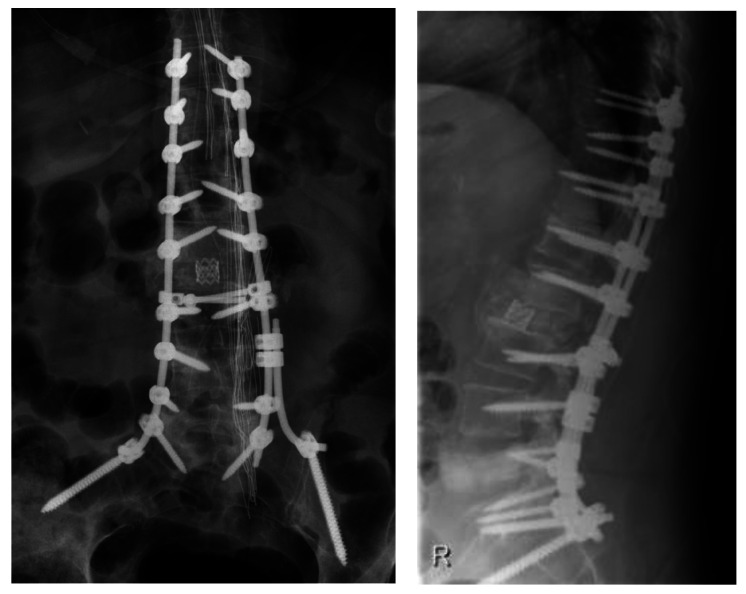

Stabilization of spine using transpedicular screws is the most commonly used instrumentation technique among spinal surgeons. The 'free hand' technique is considered relatively safe and can be performed under x-ray control. Vascular injuries with misplaced screws are rare but potentially fatal complications. Injury of thoracoabdominal aorta by malpositioned screw demands a multidisciplinary approach. Injury of vessel wall might demand screw removal and vessel wall repair. Here we present a case of 72-year-old female patient who underwent long segment fixation of thoracolumbar spine. During follow up, computed tomography (CT) scan and afterwards aortography showed a lesion of the posterior aortic wall by malpositioned screw without signs of bleeding. After meticulous preparation, combined endovascular repair with stent-graft and removal of the penetrating screw were performed. Endovascular treatment was performed simultaneously with screw removal. During screw removal, the patient was in lateral decubital position. The patient was discharged on postoperative day 8. Follow up CT aortography 6 months later showed no leak or other changes in the aorta. We found combined endovascular vessel repair with simultaneous screw removal safe and sufficient for this kind of aortic injury. Although lateral decubital position bears limitations, it gives enough space for the operator. Performing intraoperative aortography provides good insight into stent position and possible bleeding after screw removal.

Abstract Image